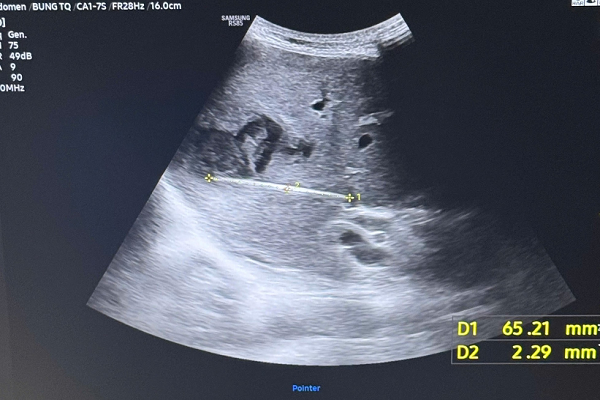

Kết quả siêu âm chi tiết và chụp cắt lớp vi tính (CT scan) khiến các bác sĩ không khỏi bất ngờ khi phát hiện một dị vật dạng que, dài khoảng 6–7 cm, nằm hoàn toàn trong nhu mô gan, kèm theo ổ nhiễm trùng sâu

Trước nghi ngờ có nguyên nhân tiềm ẩn khác, ê kíp điều trị chỉ định thực hiện các thăm dò cận lâm sàng chuyên sâu. Kết quả siêu âm chi tiết và chụp cắt lớp vi tính (CT scan) khiến các bác sĩ không khỏi bất ngờ khi phát hiện một dị vật dạng que, dài khoảng 6–7 cm, nằm hoàn toàn trong nhu mô gan, kèm theo ổ nhiễm trùng sâu.